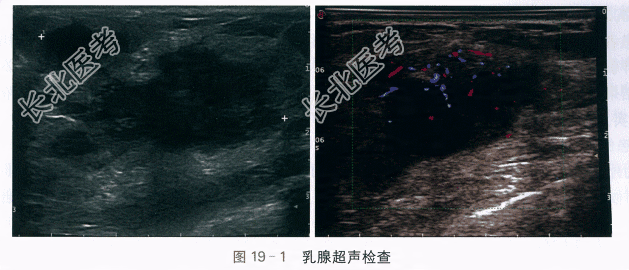

(2)乳腺B超检查结果(图19-1)提示:左侧乳腺可见一大小约49.3mm×27.9mm×43.1mm团块,位于3~4点钟方向,水平位生长,呈不规则形,边界清晰,边缘微小分叶,内部呈低回声,分布不均,部分向皮下延伸,内可见小片无回声区,后方回声无明显改变,CDFI示内边缘及中央区见较丰富血流信号,血管较细,走行规则。双侧腋窝及锁骨上未见明显异常肿大淋巴结。诊断意见:左侧乳腺实质性团块,拟BI-RADS-US 4B类,考虑乳腺脓肿可能,请结合临床。